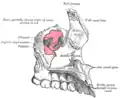

Maxilas em verde. Vista lateral.

Maxilas em verde. Vista lateral.- Modelo da maxila direita.

Maxila esquerda lateralmente.

Vista inferior, com dentes. Superfície lateral.

Superfície lateral. Interior da superfície lateral.

Interior da superfície lateral. Superfície lateral esquematizada.

Superfície lateral esquematizada. Superfície medial esquematizada.